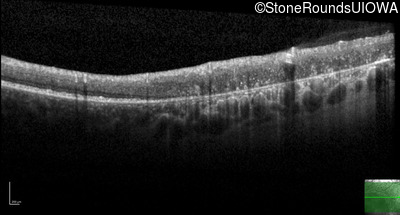

Optical Coherence Tomography - Left - 20/20 -1

Exemplar / OCT Stack